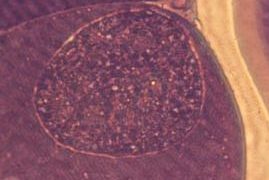

めん羊肉胞子虫 ~ 終宿主は犬、コヨーテ、アカギツネで小腸上部1/3の絨毛先端部の上皮下組織に寄生

めん羊肉胞子虫(Sarcocystis tenella)、スポロシストは楕円形で13~16 x 8~11(平均14.5 x 9.5)㎛、壁は平滑で無色ないしわずかに淡黄色。サルコシストは非常に小さく500 x 60~100㎛で、同じくめん羊...